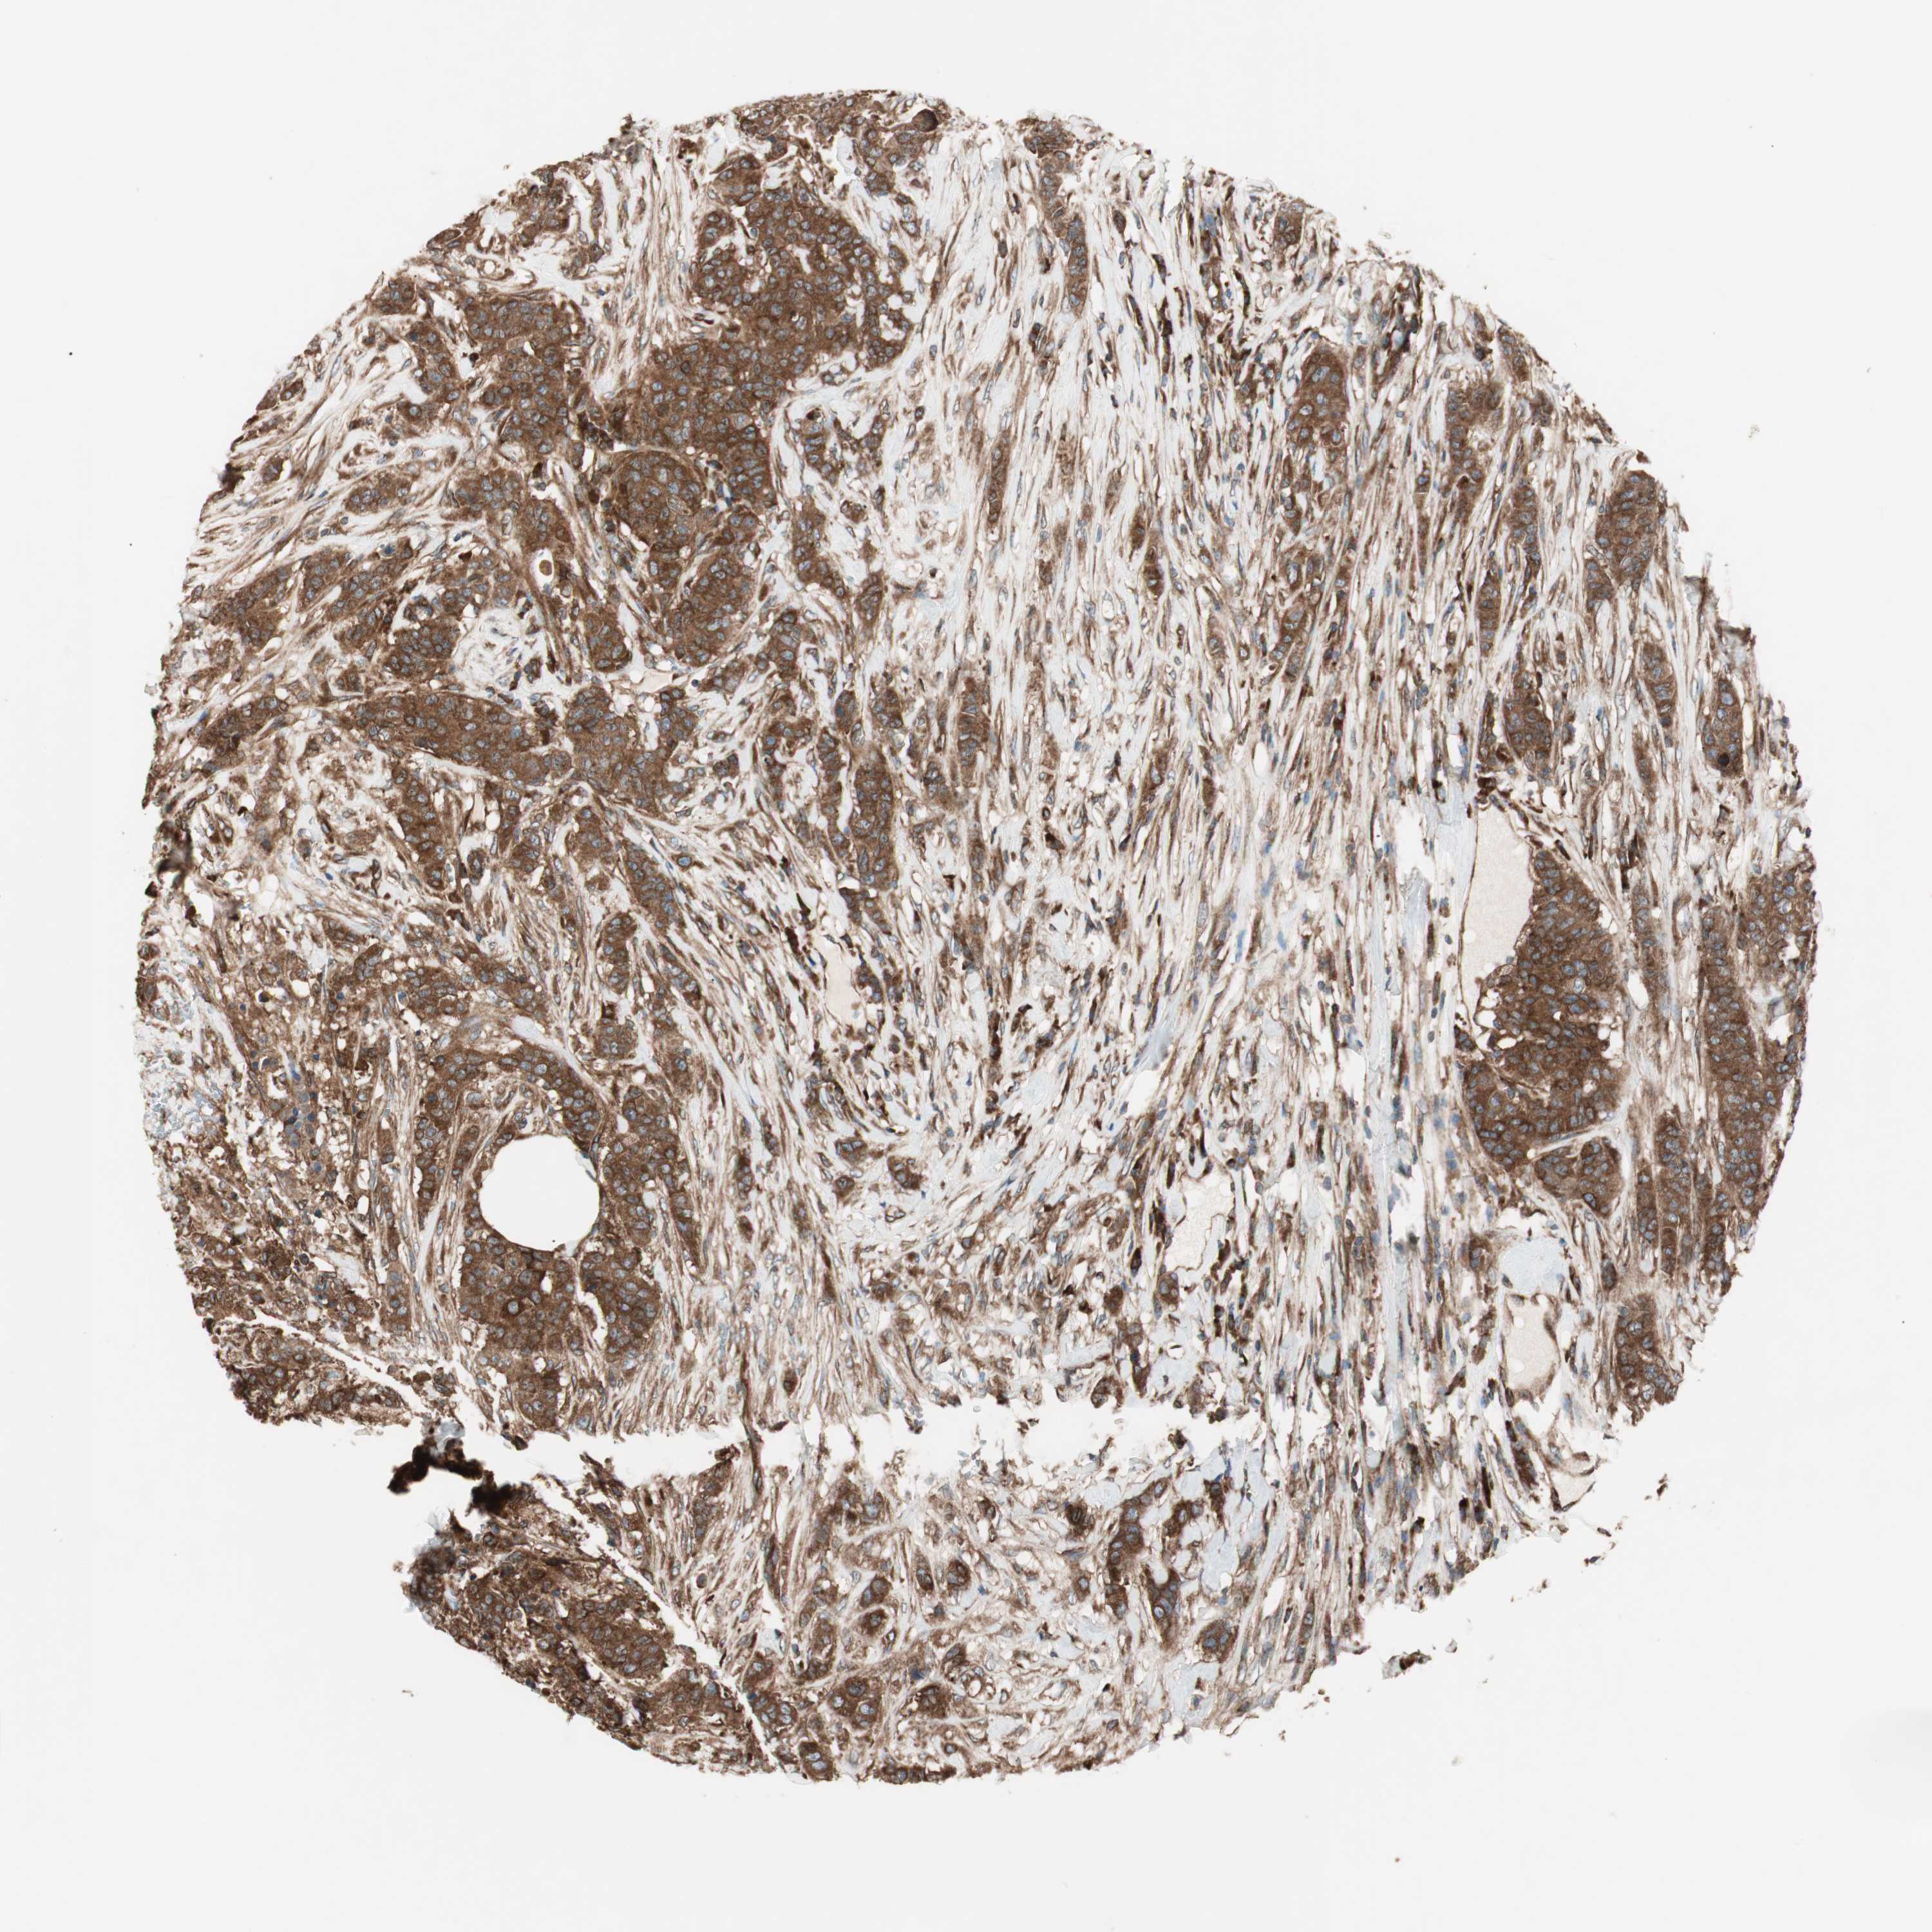

CANCER BREAST CANCER Show tissue menu

BRCA TCGA BRCA VALIDATION PROTEIN EXPRESSION